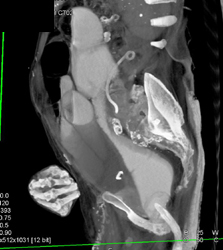

Pseudomembranous Colitis (PMC)